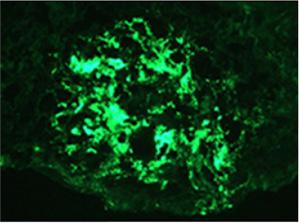

♦ Microangiopatía trombótica

♦ Estenosis de la arteria renal

♦ Nefritis tubulointersticial crónica

♦ Infecciones del tracto urinario / pielonefritis